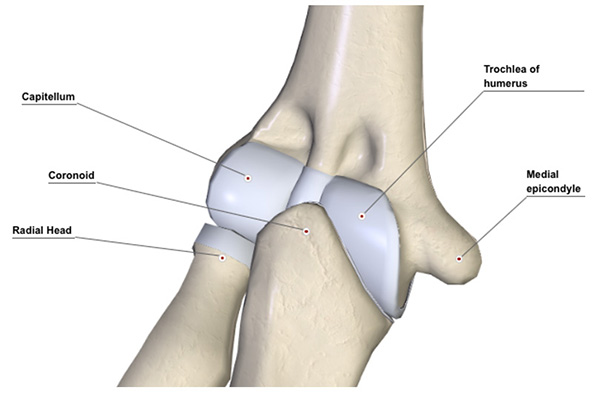

The elbow comprises three joints: the main hinge is between the trochlea of your humerus and the socket of your ulna.  Rotation of your forearm is achieved at the junction between capitellum and radial head (see diagram). The third joint between your upper ulna and upper radius also allows rotation.  The depth of your socket, the elbow ligaments, muscles that cross the elbow and the capsule all contribute to stability.  The elbow can be injured by direct force (e.g. landing on tip of your elbow) or by indirect force (e.g. landing on your hand)

Figure 1 View from the front of your elbow